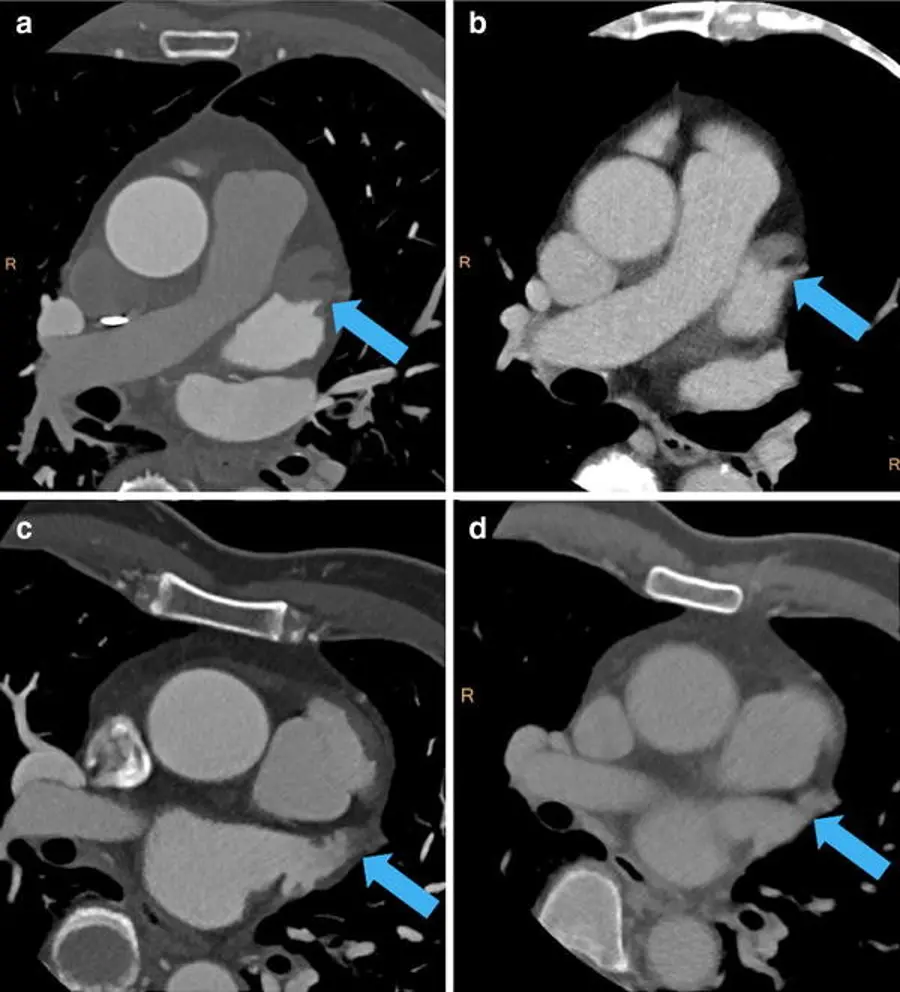

- Evaluate the left atrial appendage

- You want to look to make sure it fills completely with contrast.

- If it doesnât fill completely, it could be suggestive of a thrombus! However, sometimes it wonât fill completely because it takes a while for contrast to fill. In those cases, weâll run a delayed series. This involves scanning the LAA 30 seconds later to see if the contrast doesnât actually fill. If these delayed series are present in our system, youâll see them available in the

Series Listand theyâll be marked Delay.- While we use 30 seconds, other institutions use different times to reassess for delayed contrast filling to r/o thrombus.

- Arrow highlights LAA thrombus